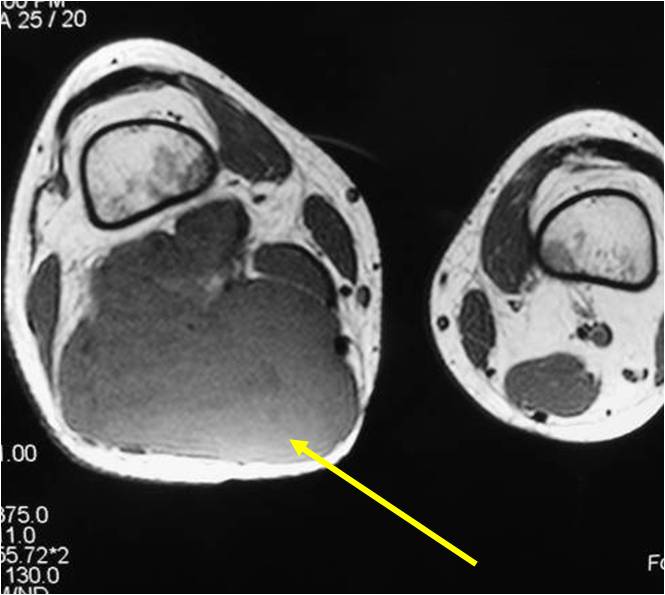

Radiographic Presentation

- Aggressive motheaten to permeative lesion

- Indistinct border in most cases

- Osseous destruction with a soft tissue component

- Chondroid matrix calcification may be present (60-70% of cases)

- Soft tissue mass